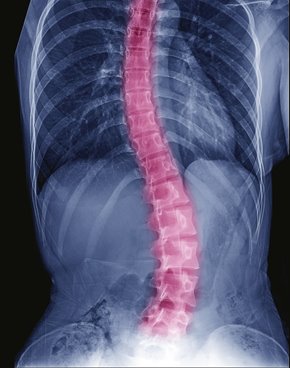

La recherche avait pour objectif d’analyser le nombre d’implants nécessaires pour maximiser les résultats des chirurgies d’instrumentation et d’arthrodèse rachidienne. Ces chirurgies visent à fusionner certaines vertèbres afin de corriger les déformations de la colonne vertébrale dues à la scoliose.

Portant sur 211 adolescentes et adolescents suivis pour une scoliose idiopathique sévère, l'étude a entre autres démontré que l’utilisation d’une faible densité d’implants permet d’avoir un pourcentage de correction équivalent à une haute densité et ce, même deux ans après l’intervention.